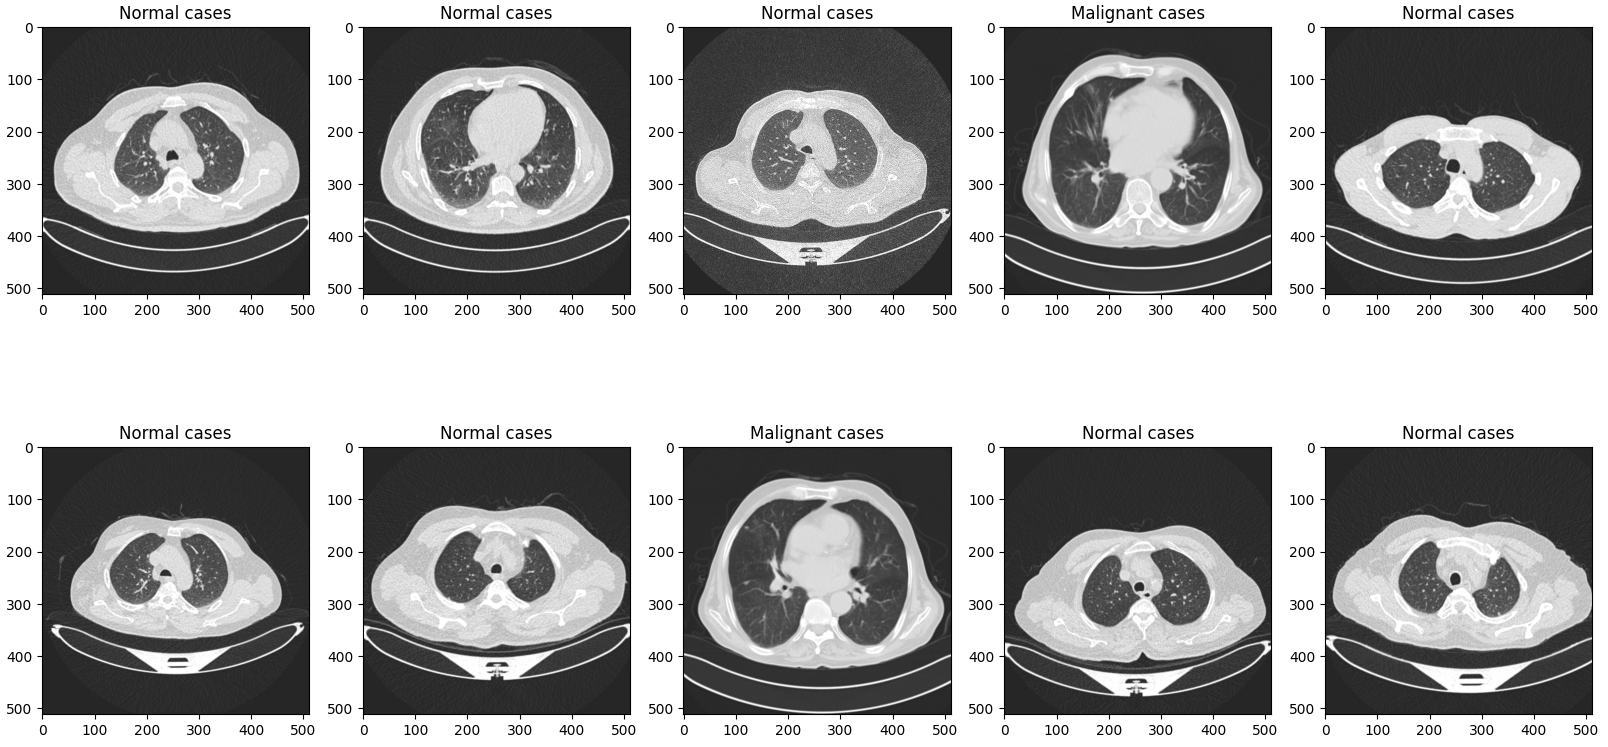

◼ [ test_root ] 첫 10개의 이미지를 시각화

|

plt.figure(figsize=(20, 10))

for i in range(10):

test_img_path = os.path.join(test_root, test_file_list[i])

ori_img = Image.open(test_img_path).convert('RGB')

plt.subplot(2, 5, (i+1))

plt.title(test_file_list[i].split('/')[-2])

plt.imshow(ori_img)

plt.show()